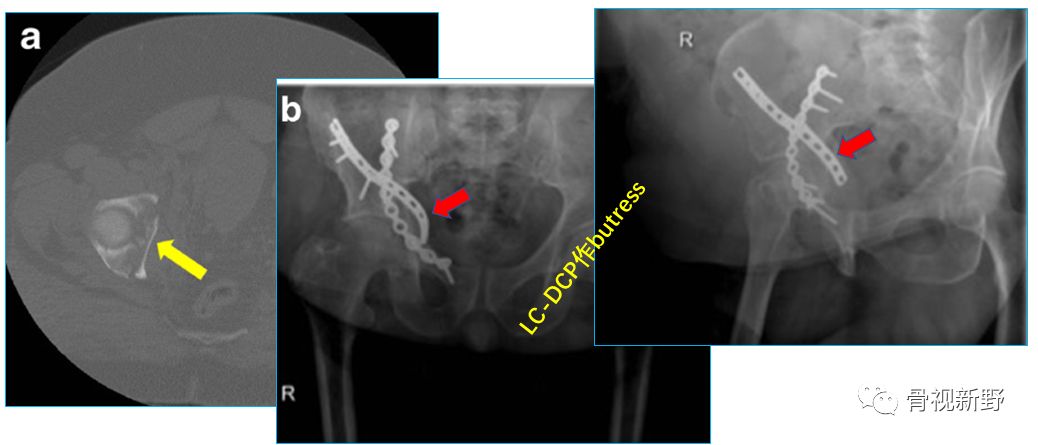

髋臼骨折的防滑、支撑固定

四边体骨折的buttress固定

小“T”形钢板作四边体的buttress固定

LC-DCP作四边体的buttress固定(Int Orthop. 2015;39(11):2219-26)

髋臼后柱骨折的buttress固定

通过髂腹股沟单一切口同时行前柱ORIF及后柱内侧壁的buttress钢板固定(Int Orthop. 2017;41(1):165-171)。